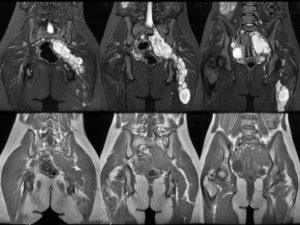

Мрт при болях внизу живота

МРТ органов малого таза

Поскольку болезненность в этой области может быть вызвана множеством заболеваний, обследуют мочеполовую систему и кишечник. У женщины определяют:

- изменение размера, формы и расположения внутренних органов – увеличение, атрофию, отек, смещение, опущение, перекрут;

- наличие воспалительных или опухолевых образований размером от 1,5 мм – их локализацию, форму, размер, степень спаянности с окружающими тканями. Сочетание новообразования с увеличением регионарных лимфоузлов указывает на онкопатологию;

- скопление в малом тазу жидкости, характерно для водянки (асцита), возникающей при заболеваниях почек, печени, злокачественных опухолях. С помощью МРТ определяют наличие крови в брюшной полости;

- пороки развития матки (удвоение, несоответствие размеров), опущение и смещение. При внематочной беременности виден плодный мешок, находящийся в маточной трубе, яичнике, шейке или брюшной полости;

- закупорку просвета кишечника опухолью, желчным камнем, клубком гельминтов, заворот кишок;

- состояние мочевыделительной системы: положение почек, их структуру, проходимость мочеточников, состояние стенок и размер мочевого пузыря, наличие камней и опухолей.

Диагностика проводится на высокопольном томографе силой поля 1,5 Тл. Это дает высокую информативность данных. При обследовании рассматривают органы со всех сторон и даже внутри.

При необходимости размер исследуемого участка увеличивают, чтобы рассмотреть досконально. При МРТ человек не подвергается облучению, а рассмотреть можно сразу несколько органов.

Это увеличивает эффективность исследования, упрощает и облегчает диагностику.